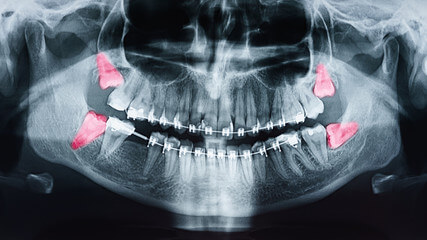

인류의 턱이 작아지면서 입안 깊숙이 사랑니가 자랄 공간이 부족해졌고 이 때문에 사랑니는 눕거나 발치하는 등 썩거나 염증이 생기기 쉬운 모양으로 나오는 경우가 많습니다.

인간은 사랑니를 제외하고 상하 14개의 영구치를 가지고 있습니다. 중앙에 한 쌍의 앞니, 한 쌍의 옆 앞니, 한 쌍의 송곳니, 두 쌍의 작은 어금니, 두 쌍의 어금니가 있습니다. 이 두 어금니보다 작고 큰 어금니 바깥쪽으로 자라는 치아를 '사랑니'라고 합니다. 사랑니의 학명은 '제3대구치'로 세 번째로 큰 어금니를 의미합니다.

사랑니가 다 있게 되면 위턱과 아래턱 양쪽에 하나씩 총 4개가 됩니다. 약 7%의 사람들은 사랑니가 전혀 없으나 만약 가지고 있다면 치아의 수는 사람마다 1~4개로 다양합니다.

사랑니는 보통 정상적으로 나오고 깨끗하게 유지되면 문제없이 사용할 수 있습니다. 그러나 공간이 부족한 치열의 가장 안쪽 끝에 위치하는 경우가 많기 때문에 관리가 어려우며 각종 질환을 유발할 수 있습니다.

사랑니는 다른 치아에 비해 크기와 모양이 매우 다양합니다. 사랑니는 똑바로 나오지 않고 기울어져 있거나 누워있는 경우 잇몸에 묻혀 있는 부분이 많습니다.